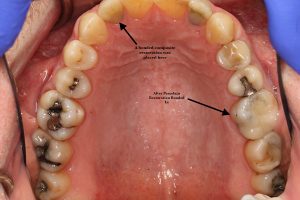

B-after